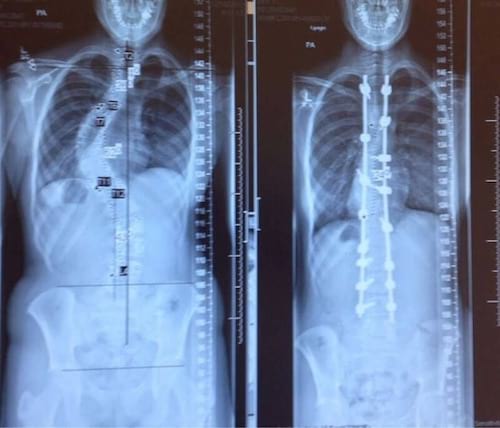

- 4. La colonne vertébrale d'une personne avant et après le traitement de sa scoliose

4. La colonne vertébrale d'une personne avant et après le traitement de sa scoliose

La médecine permet de faire d'incroyables progrès.